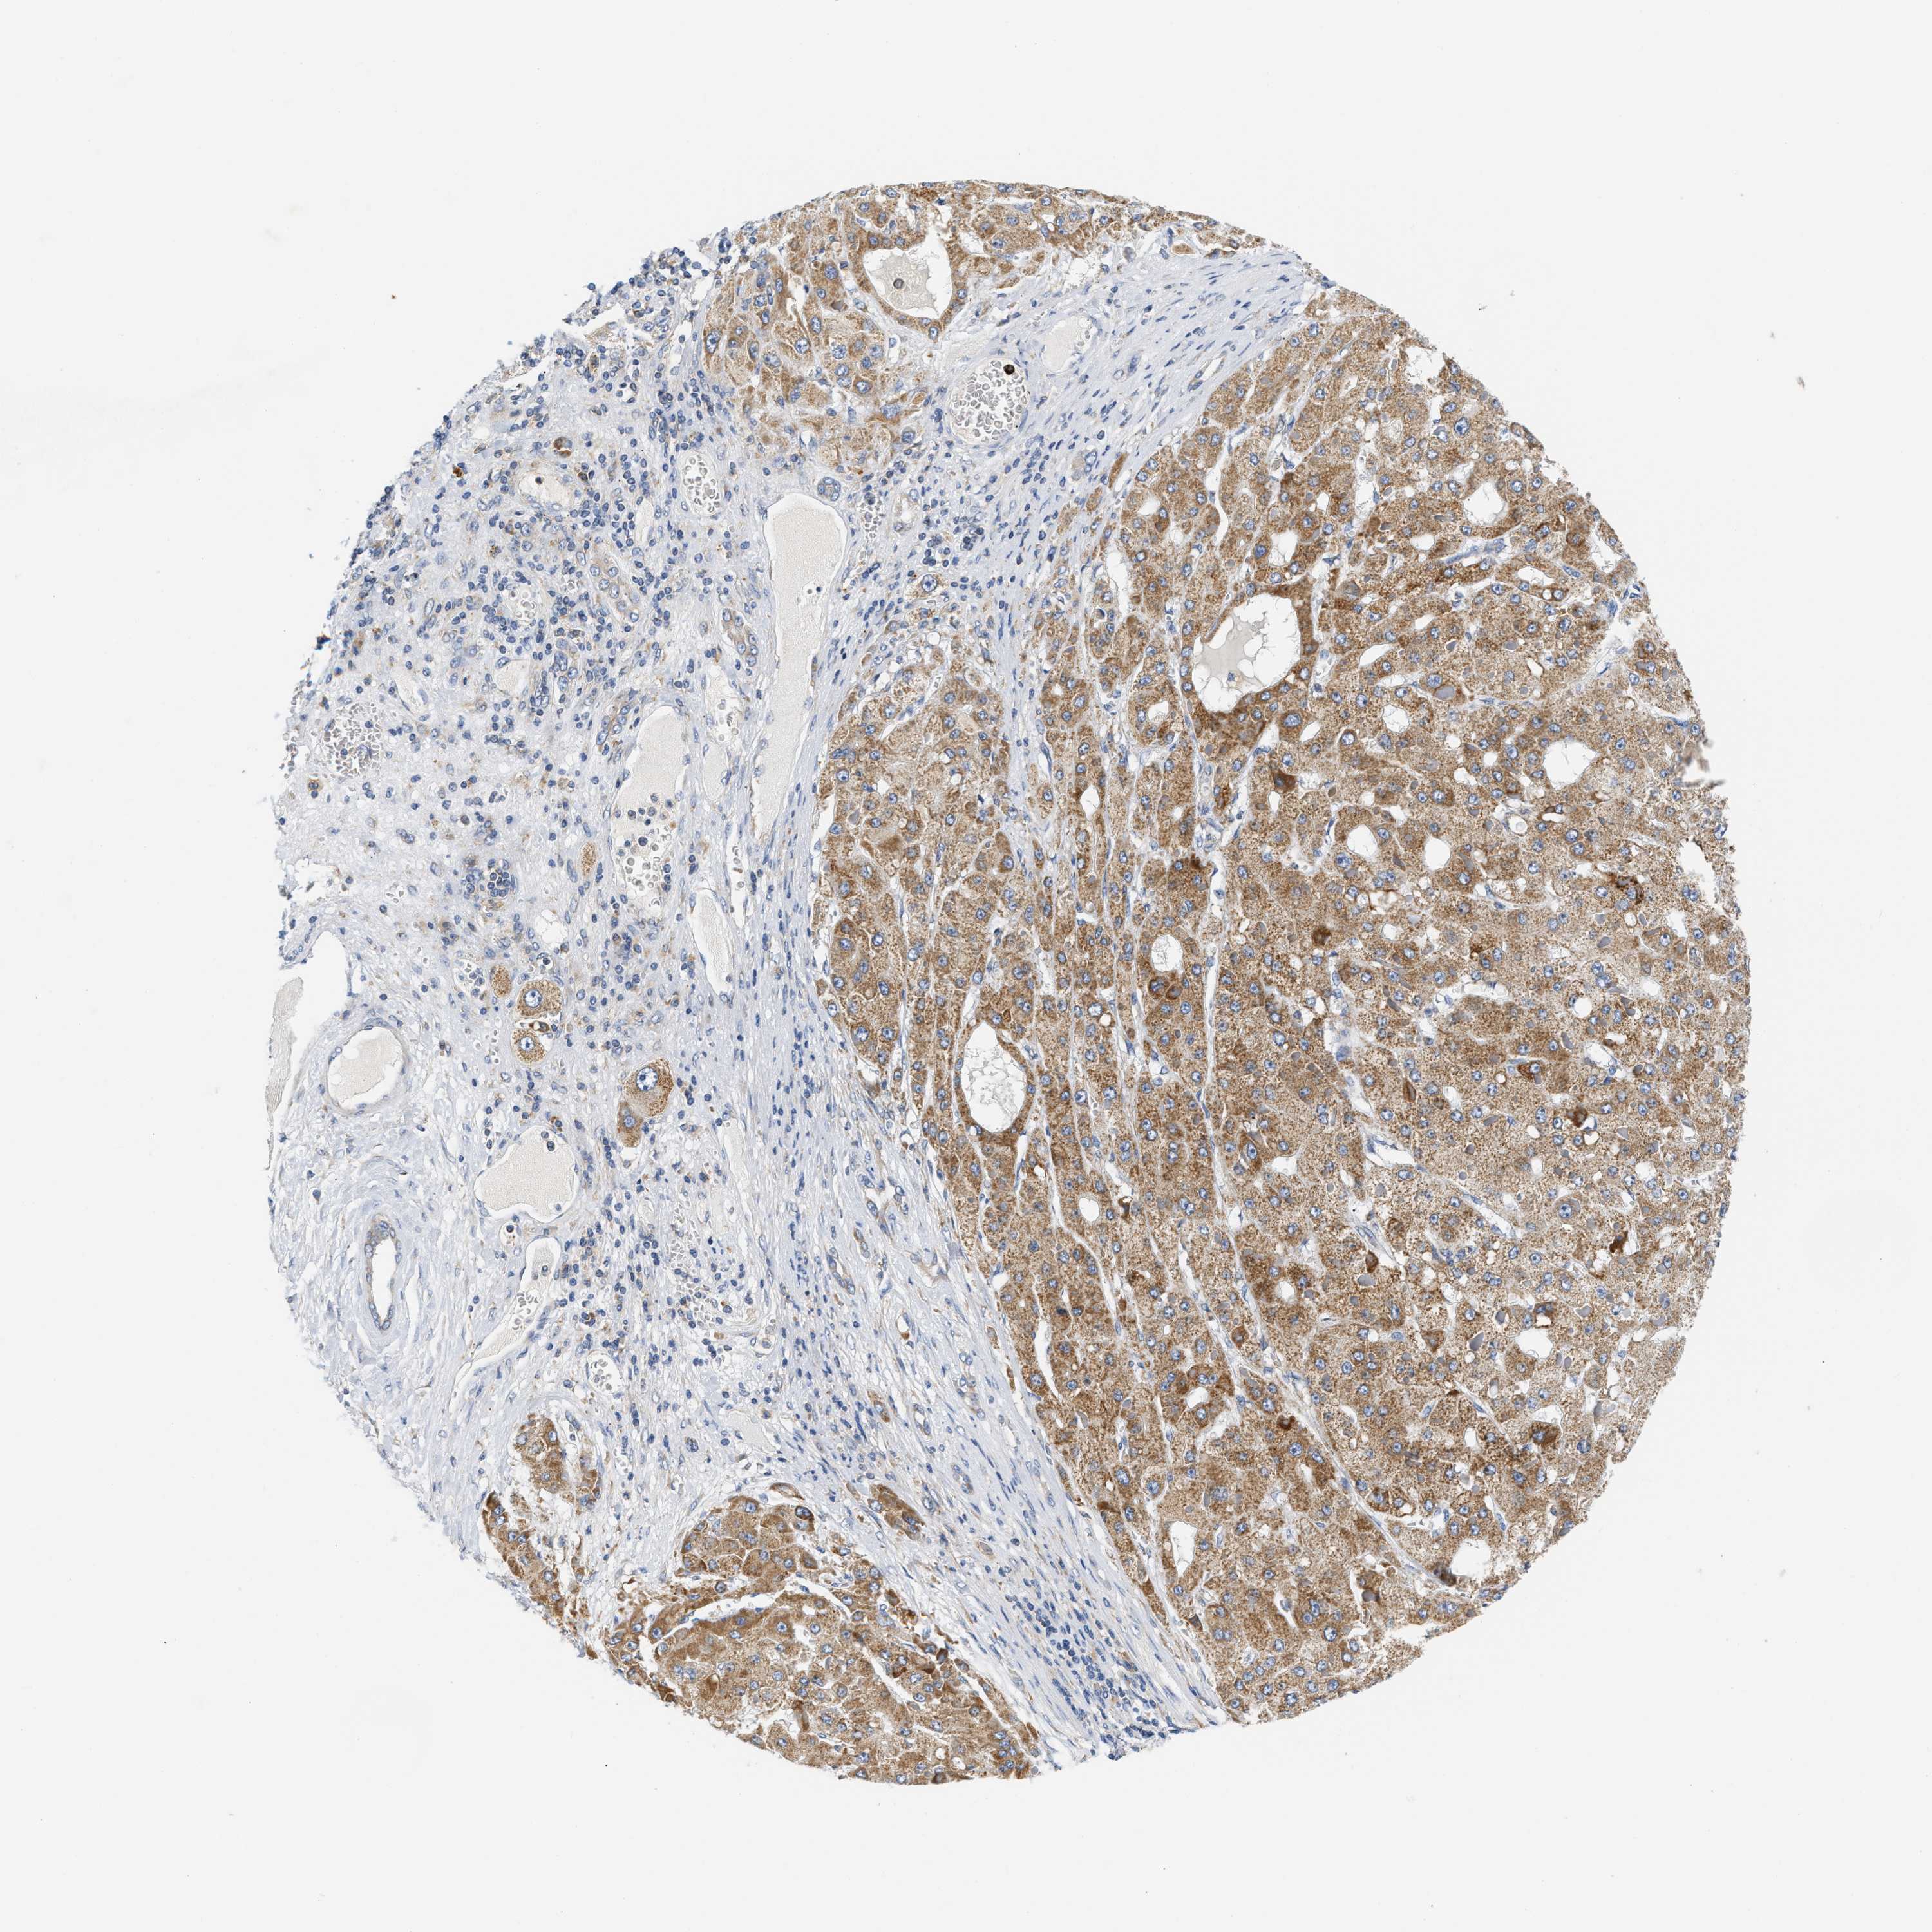

LIVER CANCER - Protein expressioni

A mouse-over function shows sample information and annotation data. Click on an image to view it in a full screen mode. Samples can be filtered based on level of antibody staining by selecting one or several of the following categories: high, medium, low and not detected. The assay and annotation is described here.

Note that samples used for immunohistochemistry by the Human Protein Atlas do not correspond to samples in the TCGA dataset.

Antibody stainingi

Antibody staining in the annotated cell types in the current human tissue is reported as not detected, low, medium, or high, based on conventional immunohistochemistry profiling in selected tissues. This score is based on the combination of the staining intensity and fraction of stained cells.

Each image is clickable and will lead to virtual microscopy that enables deeper exploration of all samples and also displays staining intensity scores, fraction scores and subcellular localization as well as patient and tissue information for each sample.

Antibody HPA020427

Antibody HPA024158

Antibody HPA024585

Staining

High

Medium

Low

Not detected

Intensity

Strong

Moderate

Weak

Negative

Quantity

>75%

75%-25%

<25%

None

Location

Nuclear

Cytoplasmic/membranous

Cytoplasmic/membranous,nuclear

Cholangiocarcinoma

Carcinoma, Hepatocellular, NOS